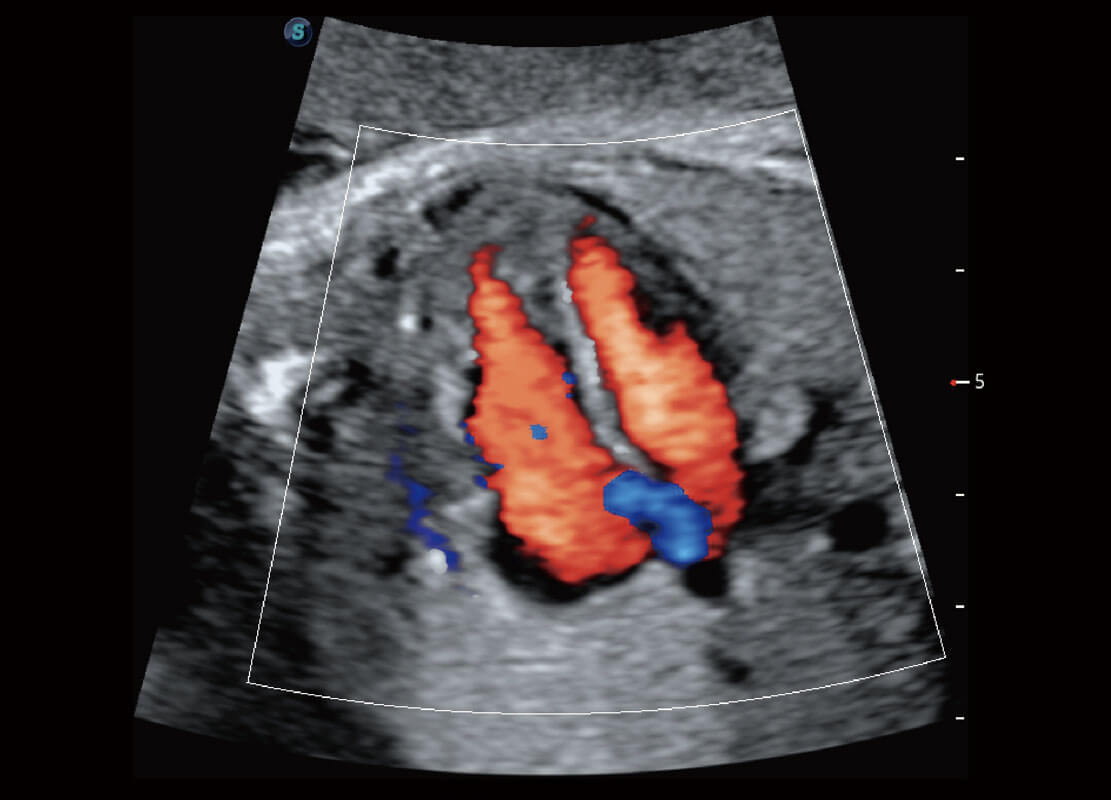

• 胎儿体循环

• 四腔心血流